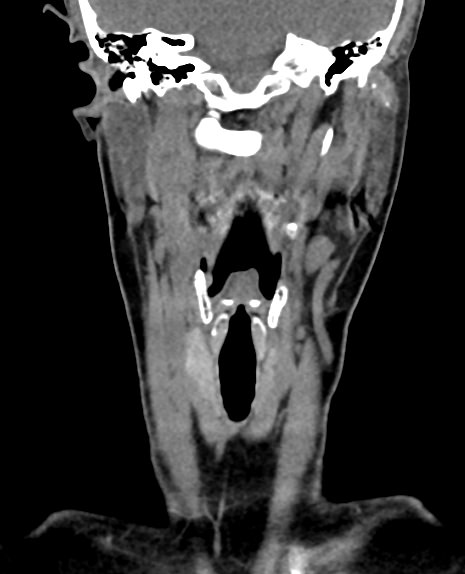

В ходе исследования хорошо визуализируются хрящевой каркас гортани, голосовые складки, голосовая щель, близлежащие органы и окружающие ткани. Помимо гортани на изображениях можно оценить состояние трахеи, носоглотки, щитовидной железы, шейных позвонков, сосудов, нервов и лимфоузлов.

Кроме того, полученные снимки дают возможность воссоздать трехмерную модель анатомической области, включая гортань и близлежащие органы, оценить точную локализацию патологических структур, их размеры и степень воздействия на окружающие ткани.